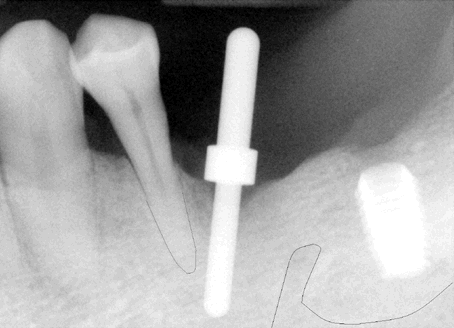

Fig.3 When the pan in Fig.2 was taken, the

patient requested more implants in the lower left quadrant. To

reduce thread exposure, we planned to place 2 implants (8 mm long) (#19 (pink tracing

line) and 20 (yellow) on the either side of the mental nerve and below the

ridge. These 2 implants should be above the inferior alveolar nerve

and incisive nerve, respectively. #20 implant should avoid touching

the neighboring root. An alternative was proposed to extract #21,

place implants at #19 and 21, and fabricate 3-unit fixed prosthetic

denture. The patient declined.

Notice the angulation of the implant for #20. |